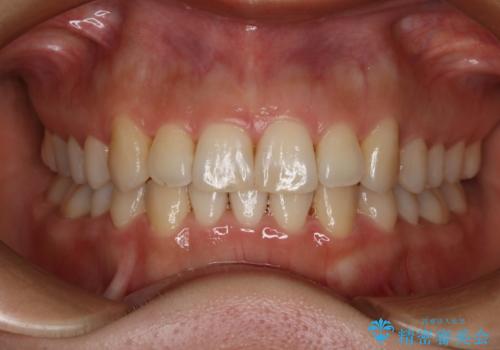

[ 前歯のねじれ・がたつき ] マウスピース矯正

![[ 前歯のねじれ・がたつき ] マウスピース矯正の症例 治療前](https://seimitsushinbi.jp/wp/wp-content/uploads/2024/02/4007c6479f6bce11863dcdd32ed5e39b-500x350.jpg?v=1708502552)

![[ 前歯のねじれ・がたつき ] マウスピース矯正の症例 治療後](https://seimitsushinbi.jp/wp/wp-content/uploads/2024/02/e7a01485e4f4dd0da04705fde4cc34cc-500x350.jpg?v=1708502585)